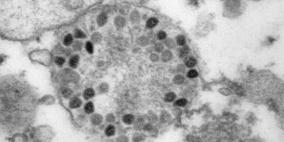

لقاح كورونا

الصين تتبرع للأونروا بمئتي ألف جرعة من لقاحات كورونا

الصحة العالمية: جائحة كورونا بعيدة عن الانتهاء والفيروس يتطور

كم بلغت أرباح "فايزر" بفضل مبيعات لقاح كورونا؟

سفارة فلسطين بالقاهرة تتسلم 500 ألف جرعة لقاح لقطاع غزة

الصحة: جميع اللقاحات المتوفرة لدينا ذات مأمونية عالية

الجمعية الطبية العالمية تدعو لفرض التطعيم الإلزامي ضد كورونا للبالغين

منها الشوكولاتة.. منتجات يجب الابتعاد عنها عند أخذ لقاح كورونا

كم عدد المواطنين الذين تلقوا لقاح كورونا في غزة؟

دولة أوروبية تستبدل لقاح "أسترازينيكا" في الجرعة الثانية

أخصائي لراية: يمكن لمن تلقى لقاح كورونا الحصول على طعم الانفلونزا

لبنان.. احتجاجات على إجراءات تستهدف غير المطعمين ضد كورونا

البرازيل: أول وفاة بمتحور أوميكرون لشخص مطعم بـ3 جرعات